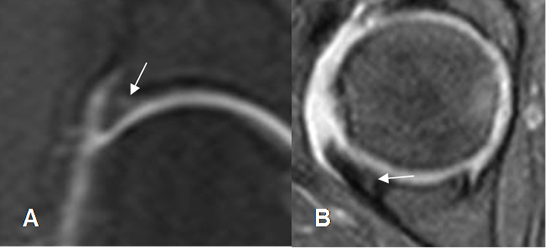

El labrum articular es una estructura triangular e hipointensa en todas las secuencias. (Fig 27 y 28).

El surco sublabral, debe diferenciarse de una ruptura del labrum acetabular. Se localiza en la parte anterosuperior o posteroinferior del acetábulo, adyacentes a la fosa acetabular. (9). Esta estructura se llena de contraste y presenta borde regulares. (Fig 29).

Fig 29. Variante normal.

A: ArtroRM coronal y B: ArtroRM axial en STIR. Defecto en la parte anterosuperior y posterior del labrum, llenos de contraste, que corresponden al surco sublabral normal.